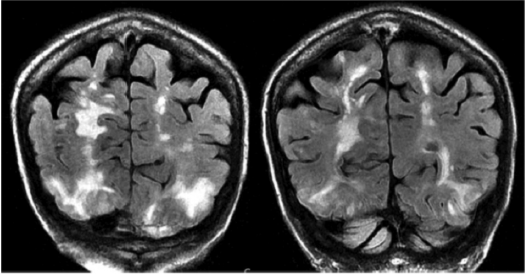

Magnetic resonance imaging (MRI) is more sensitive and has a better correlation with underlying pathophysiology compared with CT.13 In addition, MRI can differentiate PRES from other conditions that can mimic PRES. T2-weighted and T2 fluid-attenuated inversion recovery (FLAIR) images can detect vasogenic edema related to PRES. Figure 4 and Figure 5 show MRI images of PRES.

Figure 4. T2-Fluid-Attenuated Inversion Recovery Magnetic Resonance Images Showing Vasogenic Edema Around Both Occipital and Parietal Lobes and Extension of Edema in Left Frontal Lobe12